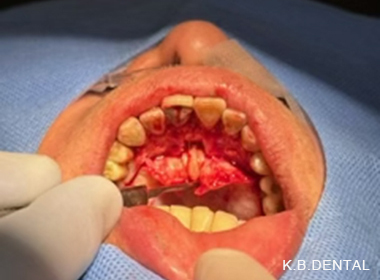

口蓋隆起 症例6(口蓋隆起形成術+親知らず抜歯)

無痛治療で口蓋隆起形成術。同時に左上の親知らずも抜歯しました。ピエゾサージェリーも使い低侵襲な手術を行いました。上顎の違和感がなくなります。

料金

静脈内鎮静法による麻酔代込み:約15万円(保険適用外)